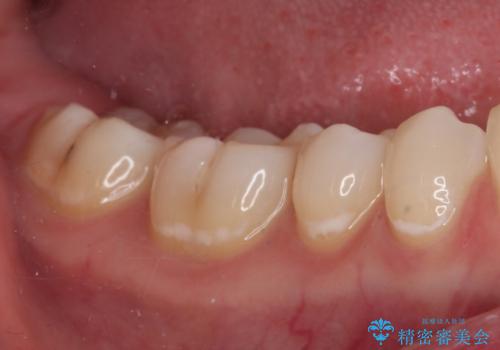

むし歯治療した歯にセラミックを入れたい セラミックインレー修復

- 他院にてむし歯の治療をし、当院にてセラミックを入れたいとのことで来院された患者様です。

むし歯がないか確認し、セラミックインレーにて修復することとしました。

セラミックインレー装着時には、唾液の侵入を防ぐために、ラバーダム防湿を行いました。

見た目、噛み合わせともに満足していただけました。

ラバーダム防湿を行い、セラミックの接着をすることで、唾液や血液などの接着阻害因子を排除することができます。